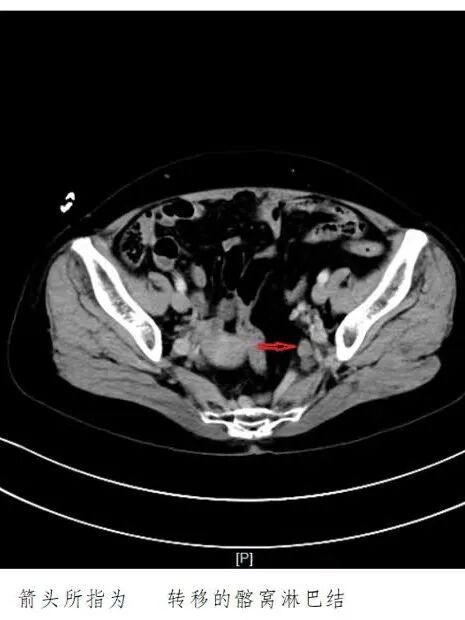

今年劳动节后,郑阿姨排便时总感觉疼痛,偶尔还发现便中带血。起初她没太在意,总想着“也许过几天就好了”。然而症状非但没缓解,反而逐渐加重。5月下旬,她终于来到昆山市中医医院肛肠科就诊。

直肠肿瘤

恶性可能性极大

通过医院内的长三角高级专家会诊服务中心,科室精准对接了上海瑞金医院胃肠外科陆爱国主任。在详细评估郑阿姨的病史与检查资料后,陆主任给出了明确方案:

直肠恶性肿瘤,有手术指征,可行腹腔镜下手术,创伤小、恢复快。